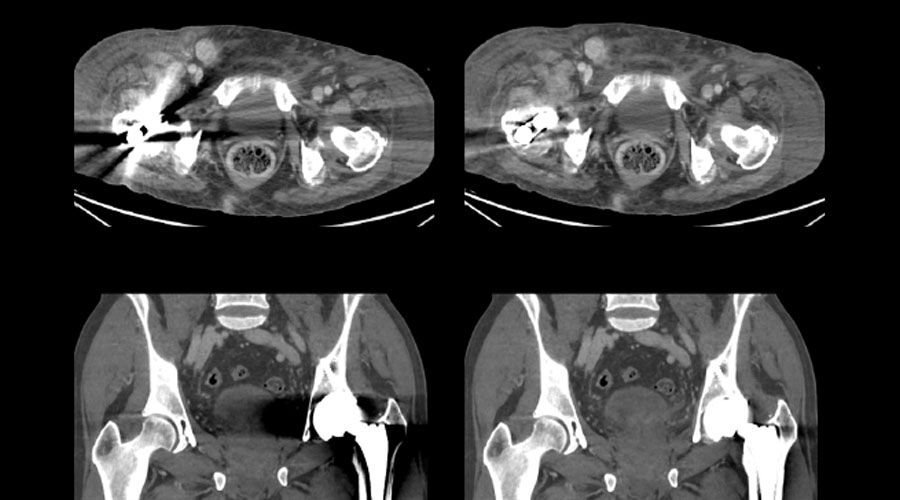

Metal Artifact Reduction for single and dual energy

Outsmart metal

Save time correcting images by reducing metal artifacts.

High density metal objects like orthopedic implants and fixtures, dental filings, and endovascular coils block critical anatomy and slow down the radiotherapy planning process. Metal Artifact Reduction (MAR) is an image reconstruction algorithm that’s proven to effectively reduce metal artifacts and reveal hidden anatomical and pathological structures.

Smart MAR and GSI MAR have the potential to save you time and improve the precision in dose calculation and organ delineation.

• Exceptional image quality for single and dual energy. MAR uses a three-stage, projection-based process to help deliver consistent, enhanced image quality that addresses both beam hardening and photon starvation artifacts

• Streamlined workflow. MAR facilitates an efficient, single-scan process everywhere, anytime

• Versatility. MAR is designed to enhance clarity across a range of cases with metal including scans with hip implants, dental fillings, screws or her metal in the body